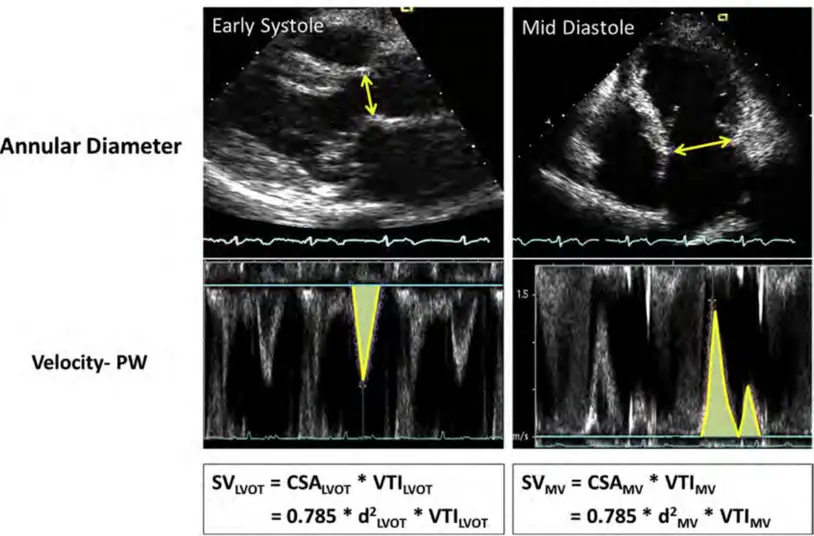

Pulsed Wave Doppler

- Pulsed Doppler methods can be used to calculate SVs at the LVOT and MV level and determine RVol and RF.

- RVol can also be calculated by comparing Doppler LVOT SV to total LV SV derived from LV volumes.

Regurgitant Volume (RVol) and Regurgitant Fraction

The example below is from Figure 4 of the 2 showing Doppler calculations of SV at the LVOT and MV annulus sites. In this example of severe MR, was 183 mL (d = 3.5 cm, VTI = 19 cm) and was 58 mL (d = 2.3 cm, VTI = 14 cm). This yielded an RVol of 125 mL () and an RF of or 68%.

Also see Figure 16 from 1 shown above in the Flow Convergence (PISA) section.